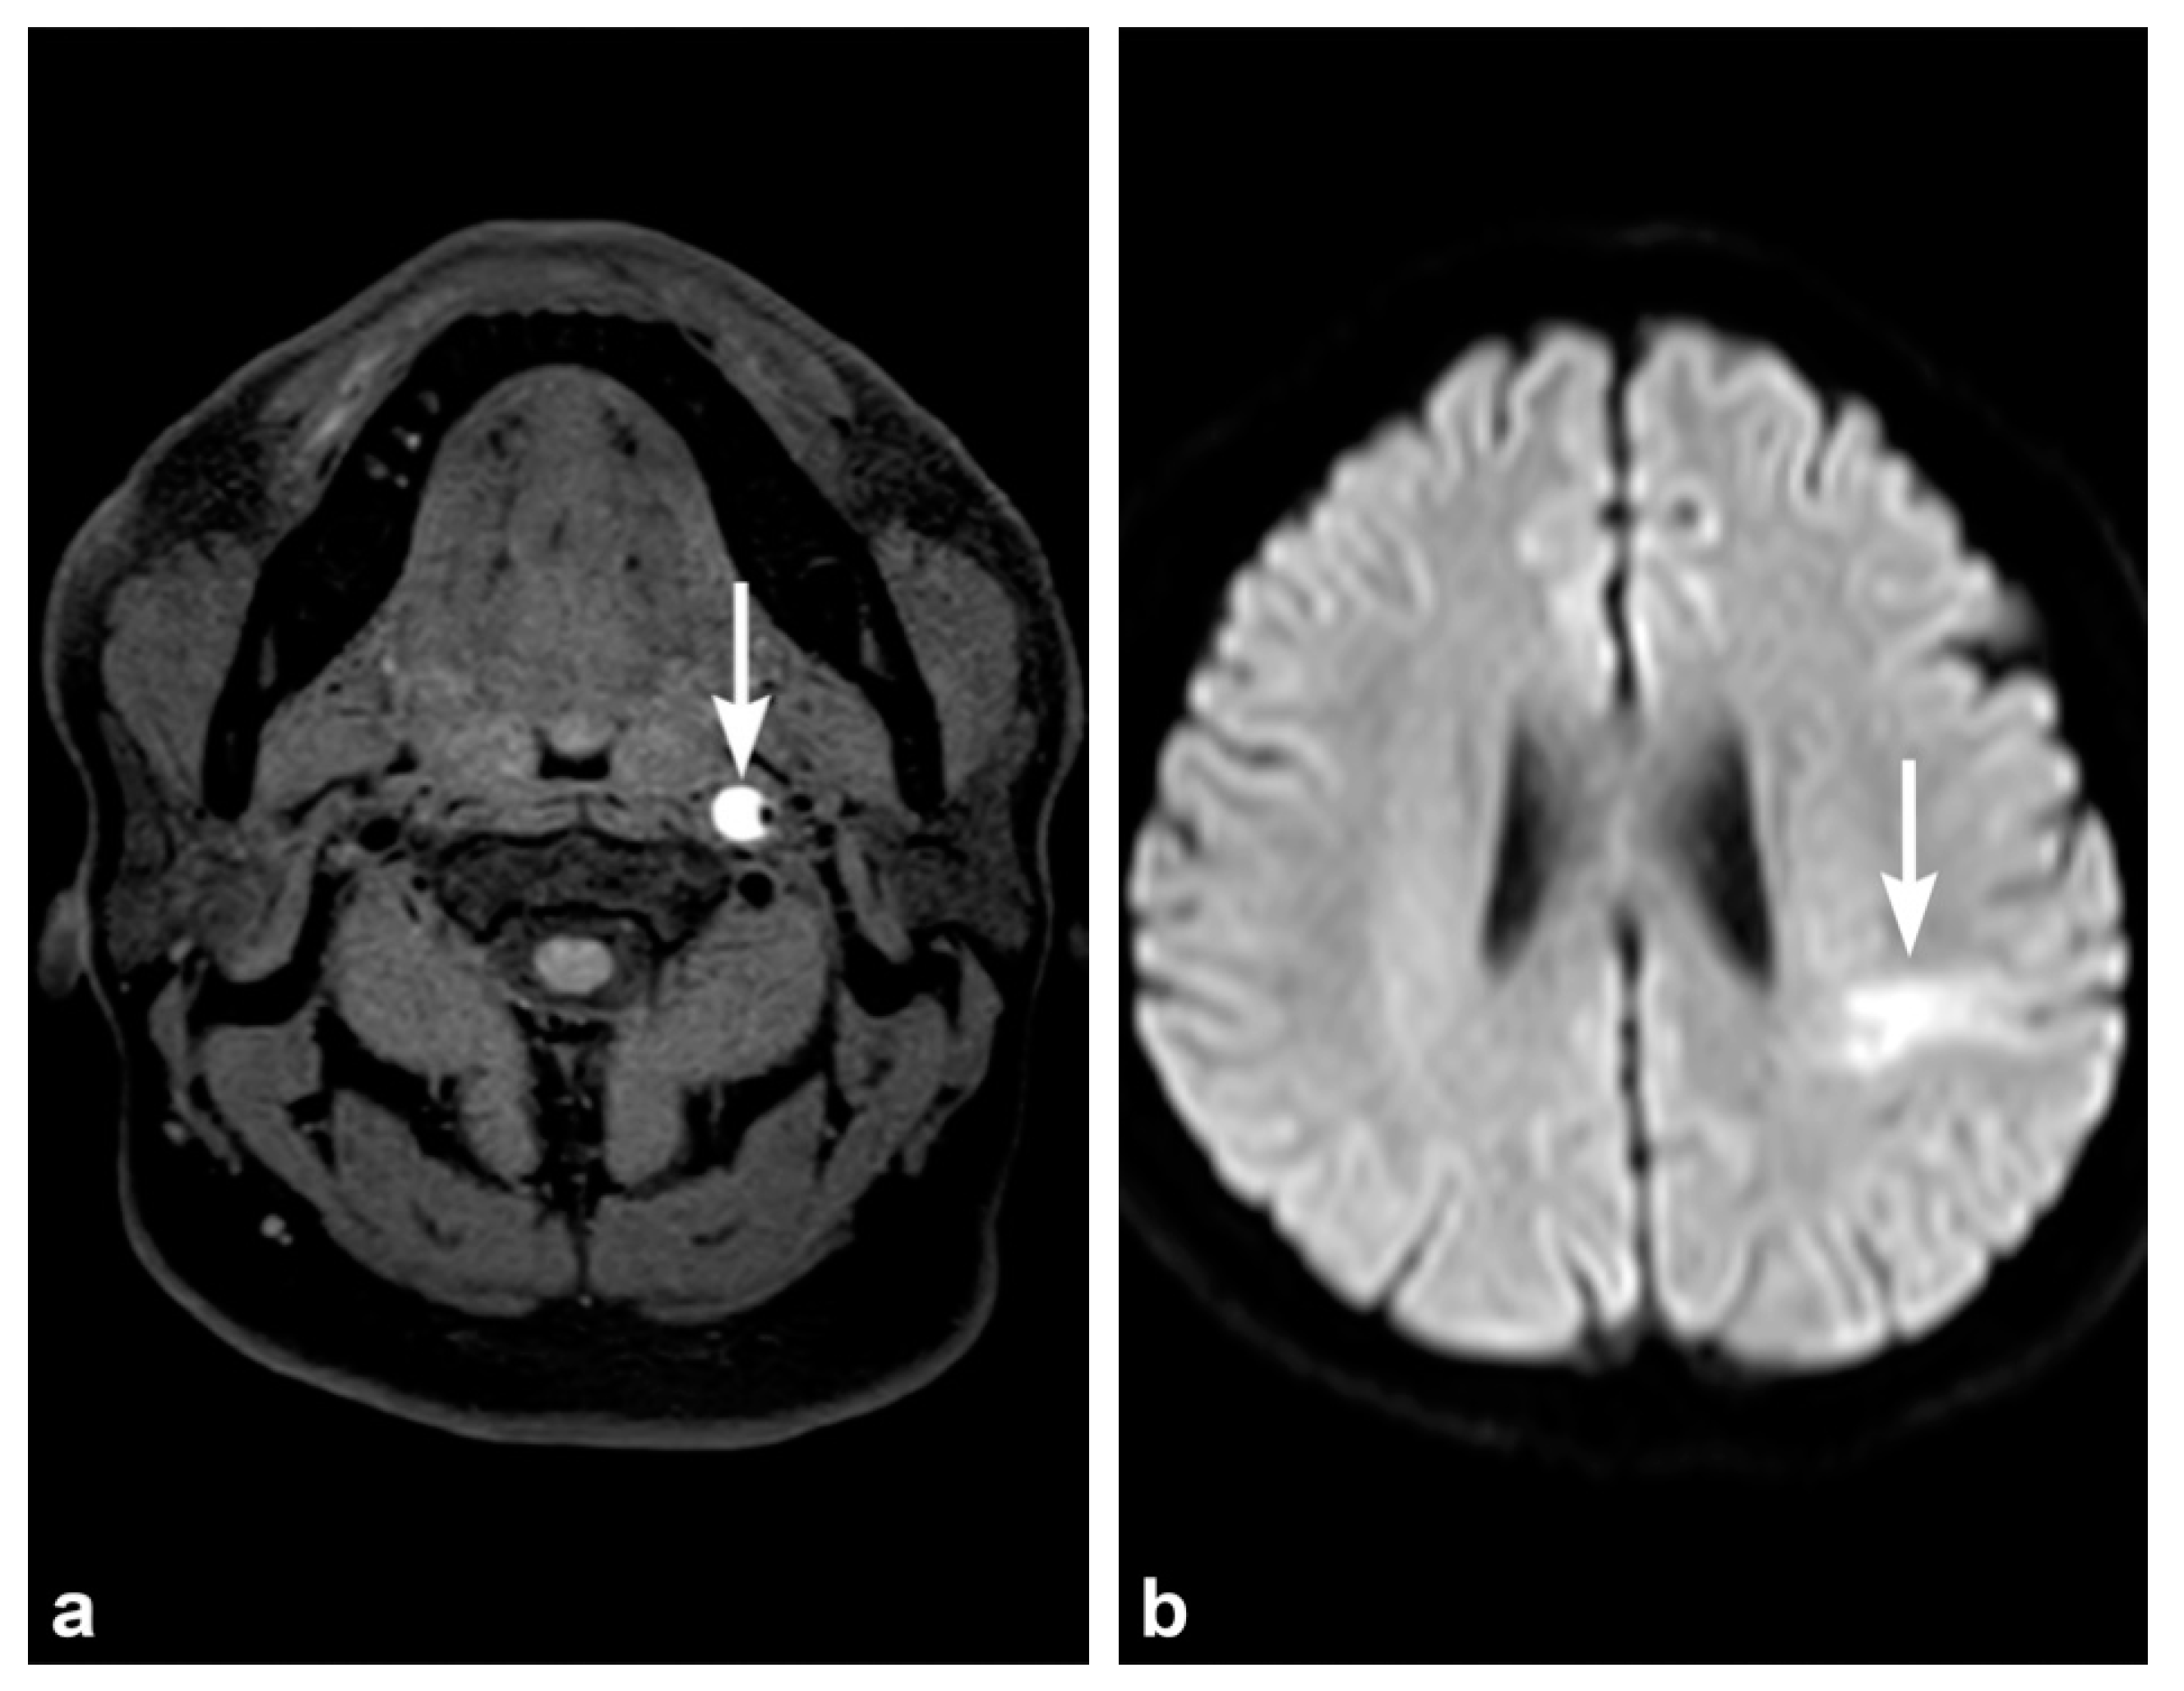

3. Imaging Findings of Arterial Injury